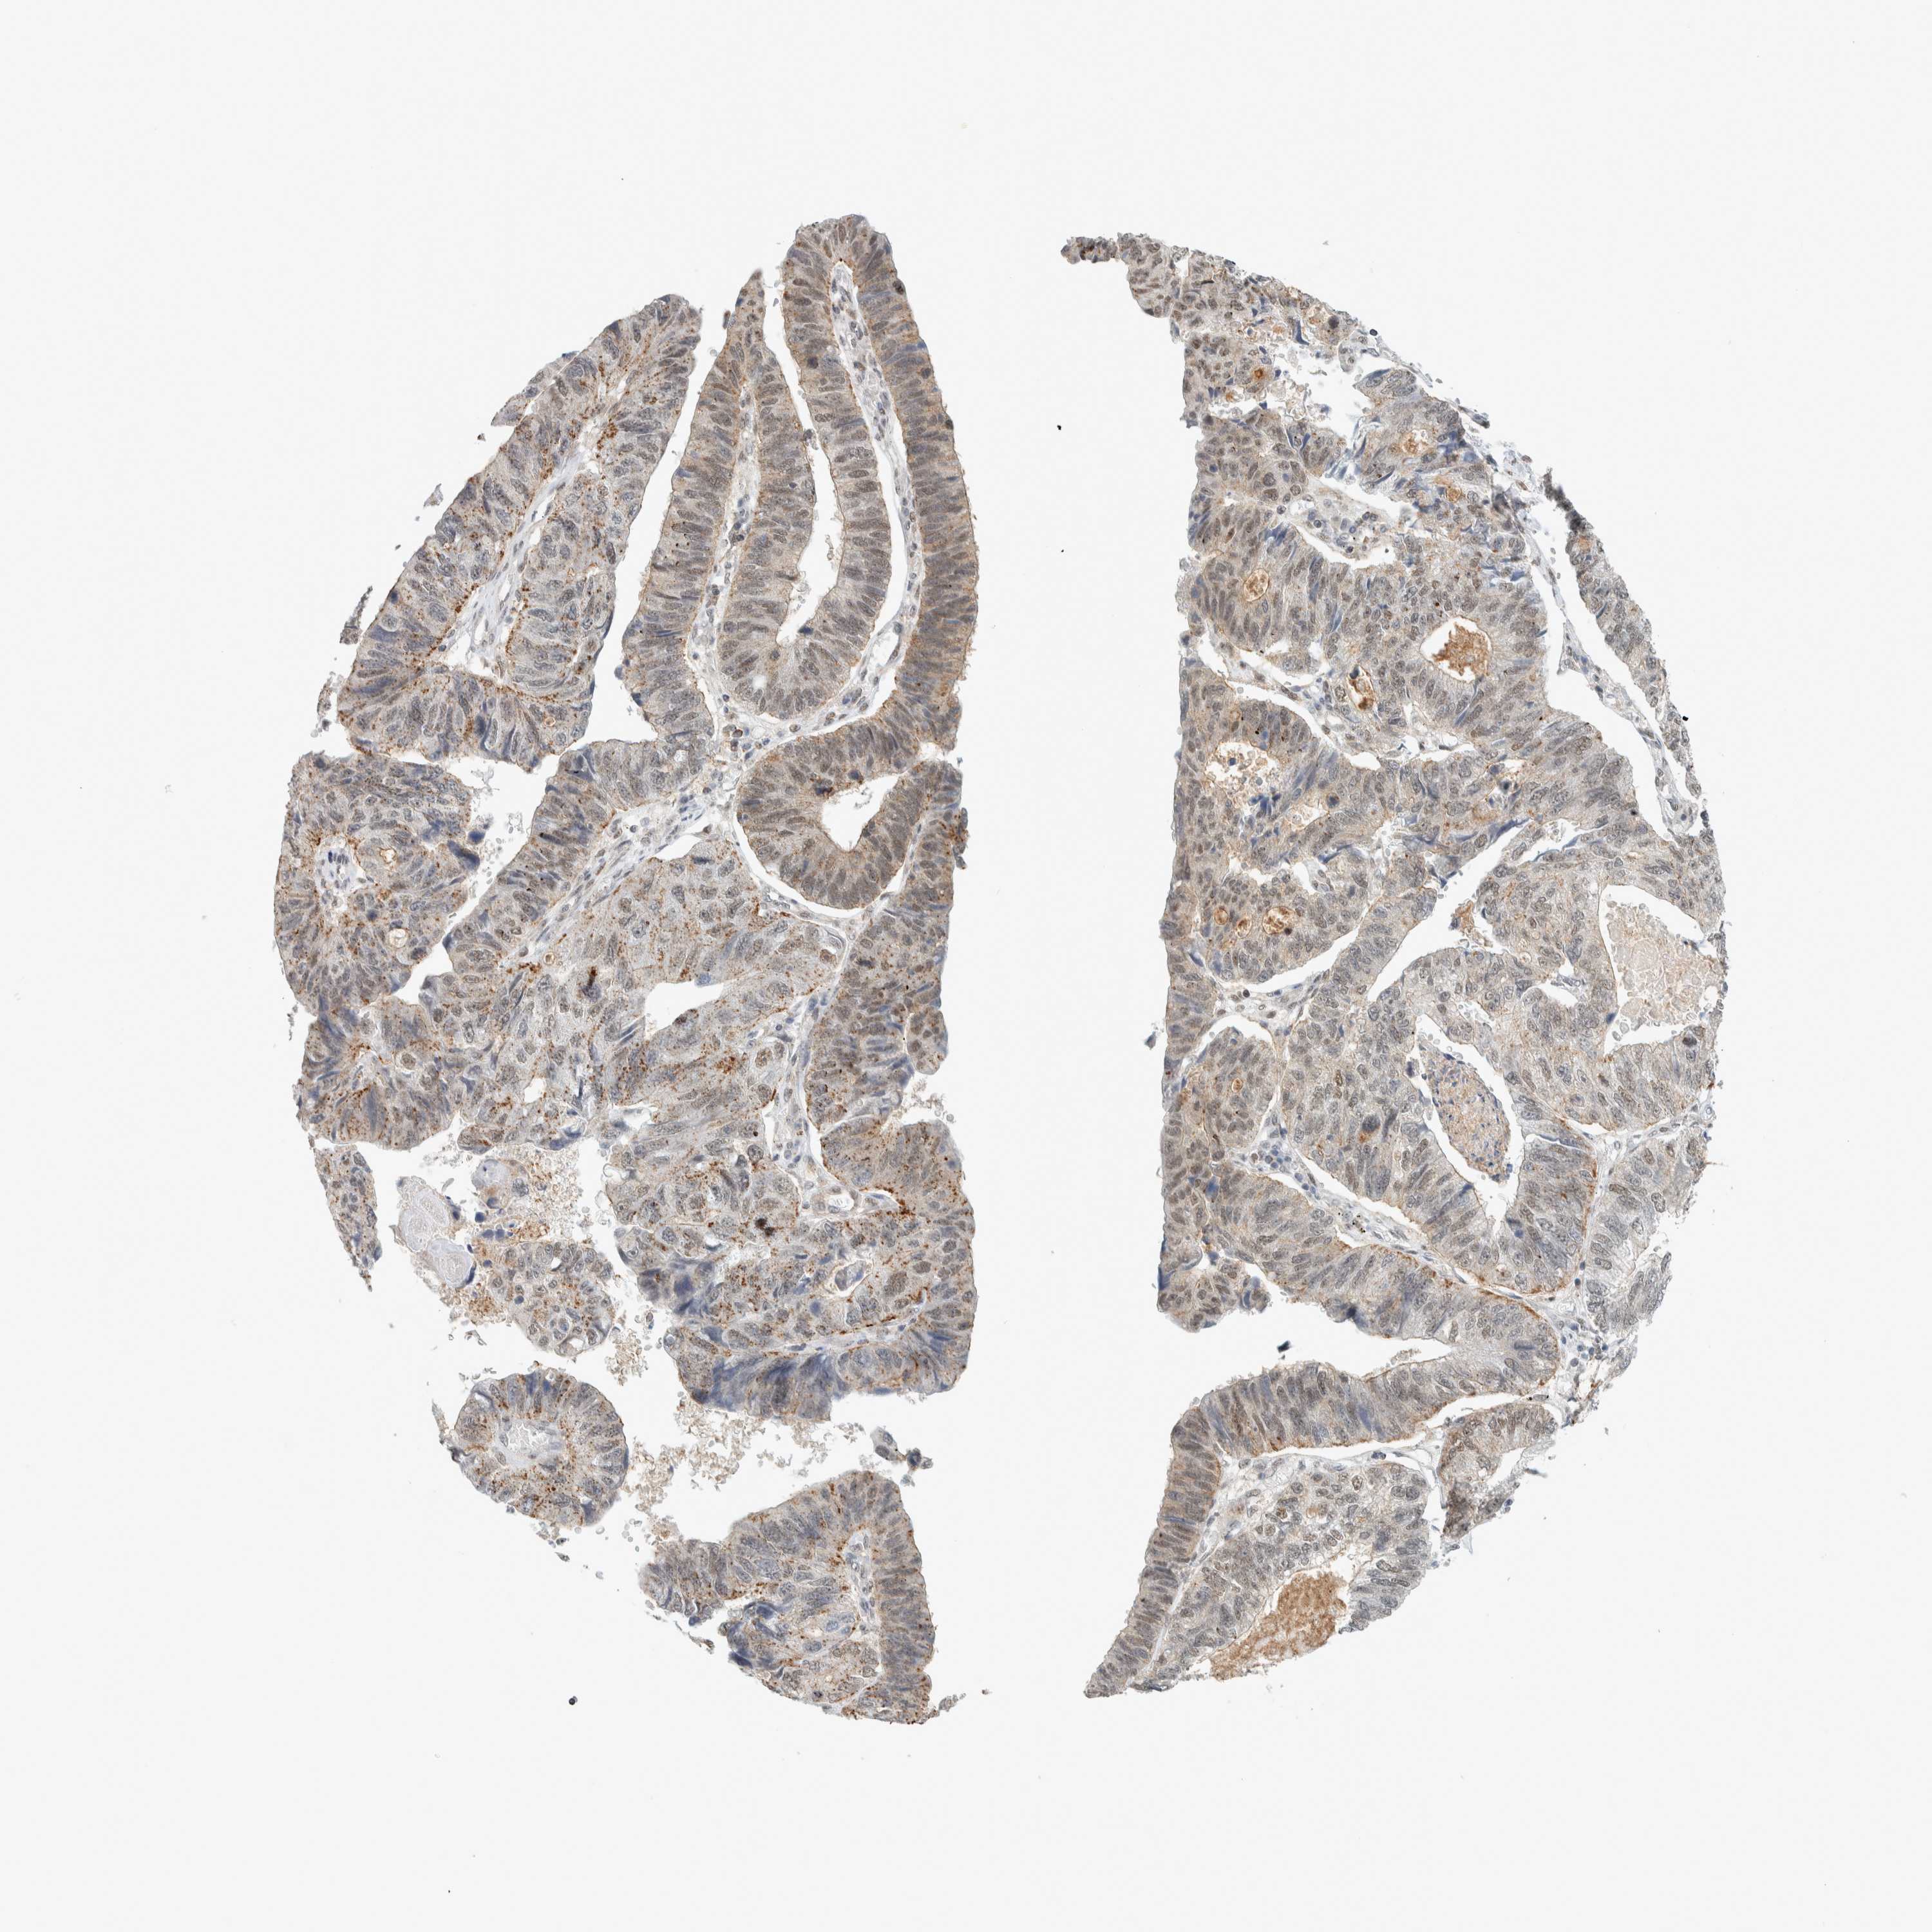

STOMACH CANCER - Protein expressioni

A mouse-over function shows sample information and annotation data. Click on an image to view it in a full screen mode. Samples can be filtered based on level of antibody staining by selecting one or several of the following categories: high, medium, low and not detected. The assay and annotation is described here.

Note that samples used for immunohistochemistry by the Human Protein Atlas do not correspond to samples in the TCGA dataset.

Antibody stainingi

Antibody staining in the annotated cell types in the current human tissue is reported as not detected, low, medium, or high, based on conventional immunohistochemistry profiling in selected tissues. This score is based on the combination of the staining intensity and fraction of stained cells.

Each image is clickable and will lead to virtual microscopy that enables deeper exploration of all samples and also displays staining intensity scores, fraction scores and subcellular localization as well as patient and tissue information for each sample.

Antibody HPA023881

Staining

High

Medium

Low

Not detected

Intensity

Strong

Moderate

Weak

Negative

Quantity

>75%

75%-25%

<25%

None

Location

Nuclear

Cytoplasmic/membranous

Cytoplasmic/membranous,nuclear

Adenocarcinoma, NOS